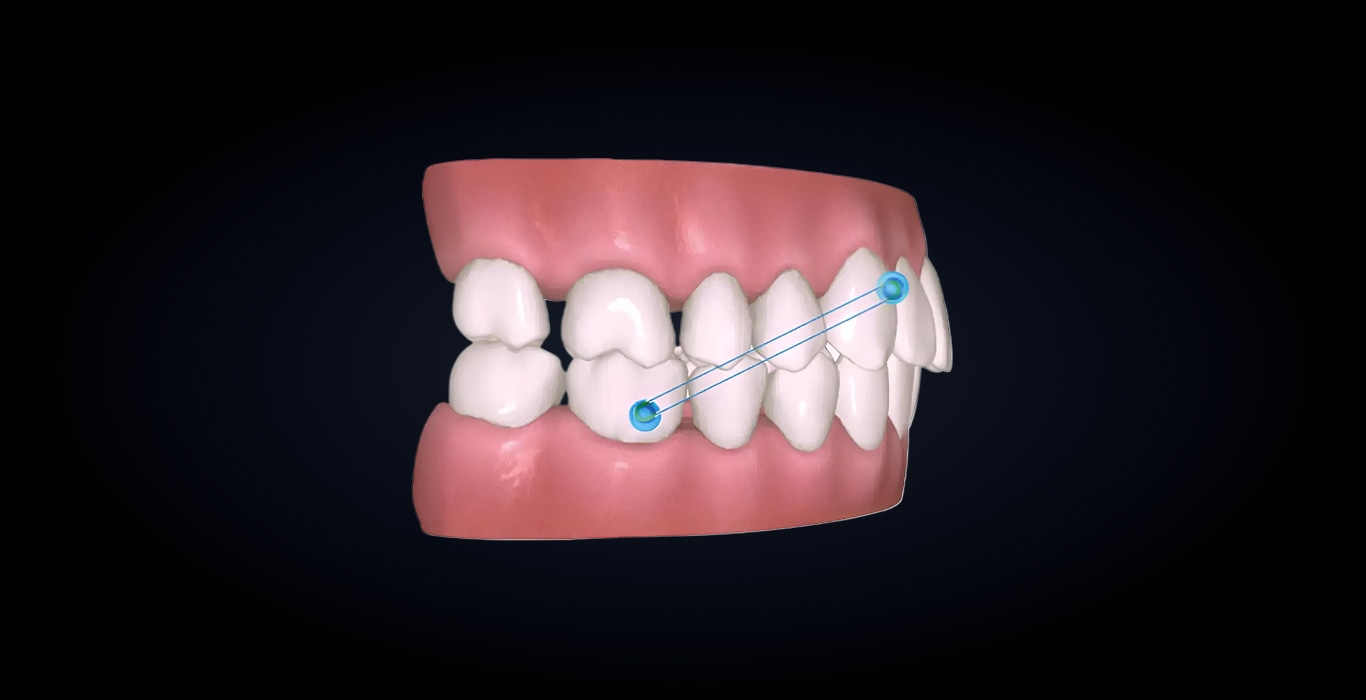

Разработан для точного и предсказуемого перемещения моляров дистально. Объединяет алгоритмы платформы masterForce⁴, последовательное перемещение зубов с использованием материалов masterControl⁵, систему аттачментов и эластических тяг к angelButton⁶, обеспечивая оптимальное распределение усилий.

Повышает эффективность лечения за счет последовательной дистализации, точного контроля опоры и вертикального положения зубов в боковом отделе, а также предотвращения нежелательных наклонов и экструзии. Данный подход снижает риск потери опоры и обеспечивает контролируемое перемещение зубов.